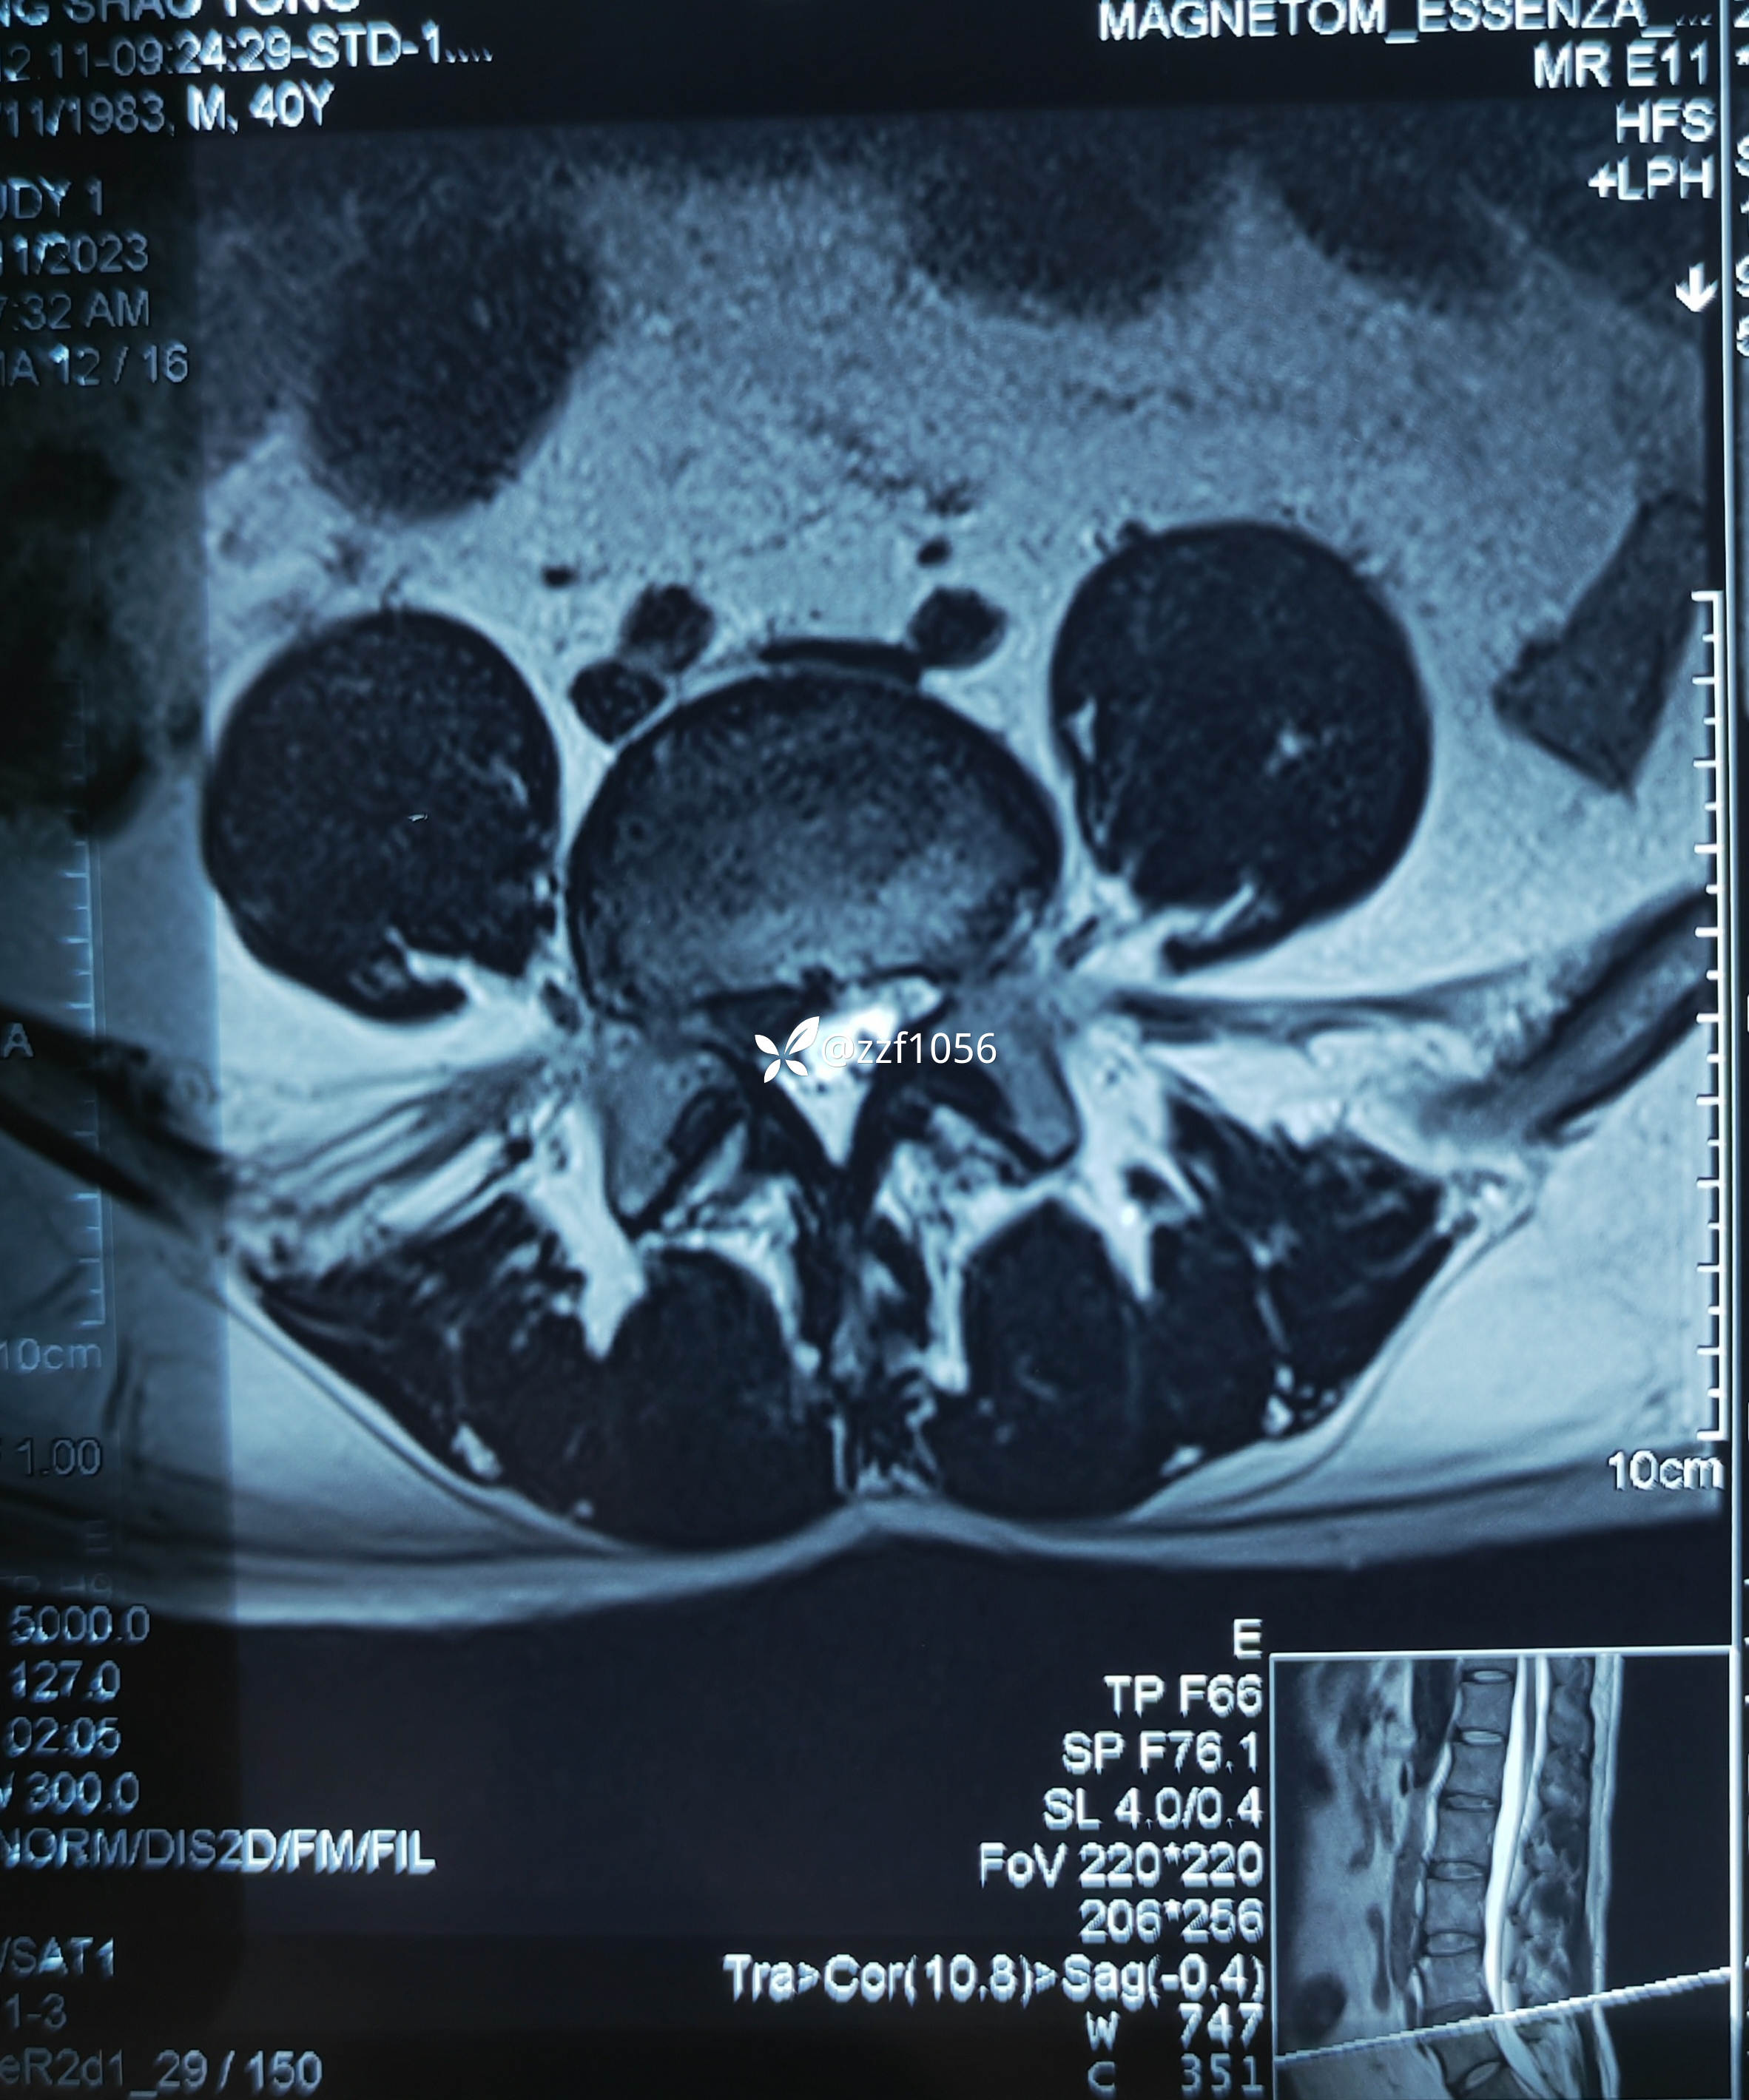

患者男性,39岁,腰痛伴右下肢疼痛麻木不适4个月,加重半个月。

4个月前右膝前叉韧带断裂在我院行重建术,当时腰椎间盘突出症状较轻,一直行保守治疗,半月前LDH症状加重,当地输液半个月无好转,只能被迫俯卧体位,严重影响生活劳作。查体典型右侧L5根性症状,患者同意微创手术,后路ube还是侧路椎间孔镜?

入院诊断:腰椎间盘突出症伴神经根病(L4/5)

侧隐窝处神经根被髓核挤压较重